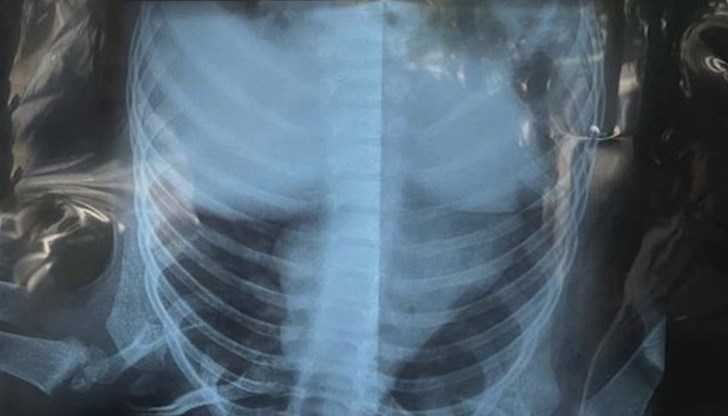

Дете се оказа с две взаимоизключващи се диагнози в две болници у нас. Според едната то е с бронхопневмония, според другата е здраво.

Датата е 6 октомври. Късно вечерта Снежана Икова води внучката си в плевенската болница за активно лечение „Д-р Георги Странски“. Детето е на година и четири месеца с кървящи венци. Взимат му кръв и снимат дробовете му на рентген.

„Педиатърката каза „Ами, евентуално са започнали да никнат зъбки“, викам добре, защо е нужно тогава да ни правят рентген на това малко дете? Влиза в системата и казва детето е с двустранна пневмония, незабавно да останете в отделението. Прецених, че детето не е за болница. Трябва да има температура, хрема, нещо кашлица – такива неща няма“, разказва Снежана пред bTV.

Четири часа по-късно в градската поликлиника на Велико Търново преглеждат детето със заключение, че няма пневмония. Под направена втора снимка великотърновският доктор Марин Маринов пише, цитирам, „белодробният паренхим е нормално прозрачен“. „Това означава, че няма нищо смущаващо в белите дробове на детето“, обяснява лекарят.

„Нашата болница е една от най-натоварените в Северна България и ние не бихме си измисляли пациенти, достатъчно много COVID болни имаме. Всички наши лекари категорично след рентгенова снимка виждат, че детето има двустранна бронхопневмония“, обяснява той. Казва, че не знае какво са казали колегите му и не може да коментира диагнозата от другата болница.